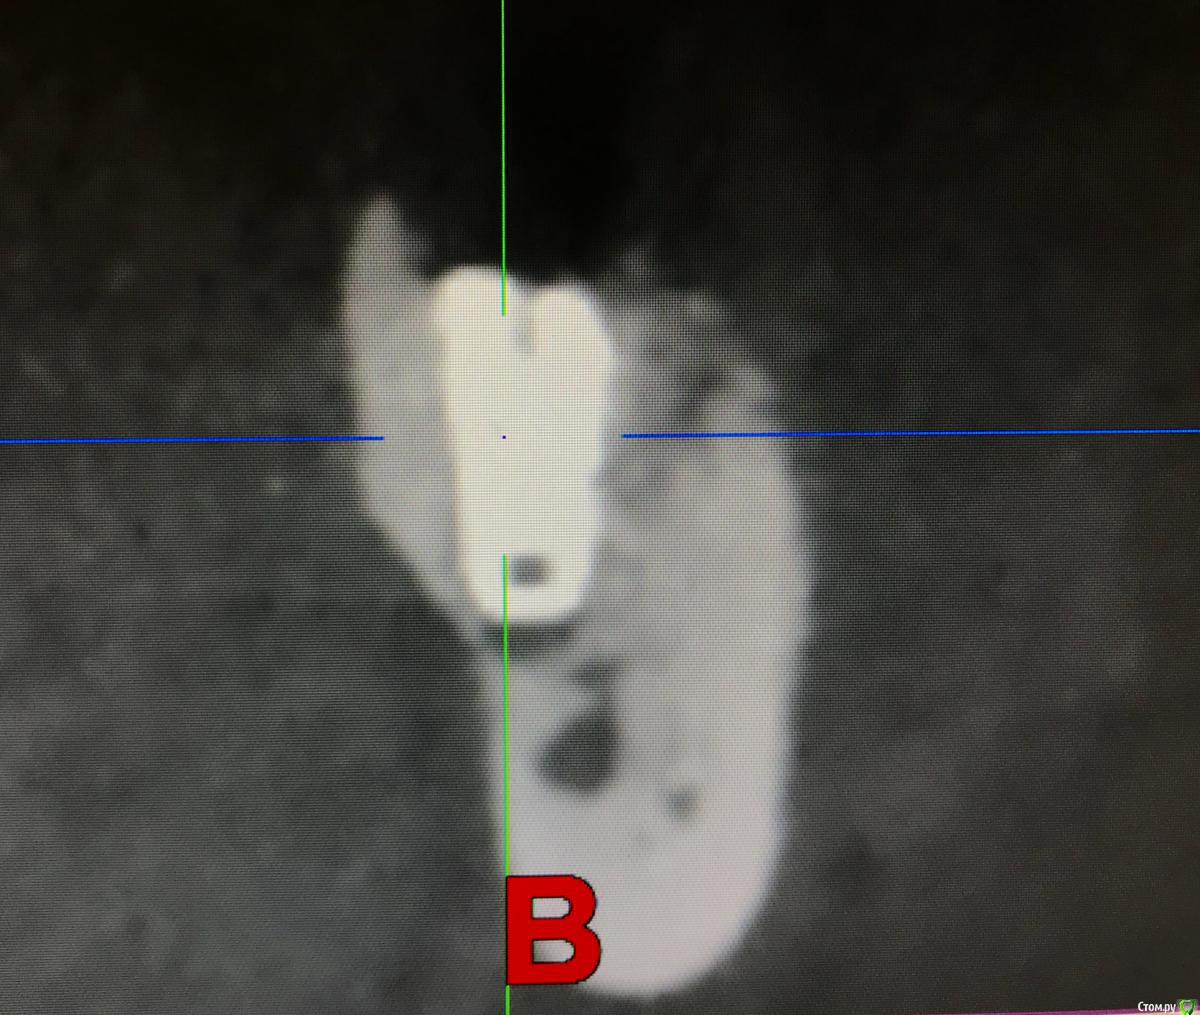

колесников Опубликовано 22 апреля, 2019 Поделиться Опубликовано 22 апреля, 2019 (изменено) И снова профайл спасает жизнь (облегчает жизнь имплантолога)Стандартная ситуация:36 периодонтит в стадии обострения с грануляциями,эксудацией,резорбцией компактной пластинки,дефицитом прикреплённой слизистой вестибулярного. Одна хирургия. Ноябрь 2018. Удаление,кюретаж,имплант Astra tech profile 4.5x9 под заглушку,торк около нуля. Вестибулярного сст,консервация графтом Sureoss 0,5 чипс с APRF,закрытие шайбой по Ноймайеру. Через неделю шайба несостоятельна-удалена. Пациентка созрела на удаление 37го. Выполнена декоронация в связи с отъездом пациентки,далее через 2 недели удаление и имплантация 37го. Промежуточный осмотр в январе. В марте установлены формирователи . Апрель контрольный осмотр. Периотест -5. Направлена на протезирование. Изменено 22 апреля, 2019 пользователем колесников 4 Ссылка на комментарий

колесников Опубликовано 23 апреля, 2019 Автор Поделиться Опубликовано 23 апреля, 2019 Разница от платформы до зенита 3 мм.Ещё раз. Вестибулярно дефект 9мм. Полное отсутсвие прикреплённой слизистой,язычное поднутрение и воспалительный процесс. Чтобы провести олномоментную имплантацию пришлось бы взять короткий имплант,заглубить его на 8мм от зенита,засыпать графтом,перекрыть мембраной,натянуть щеку и ждать-молиться чтобы края не разошлись и все не стухло. А после 2 -3 десневые пластики и глубокая шахта. Господа! Коллеги! Где сроки? Где бюджет? Где прогнозы? Ладно имплант и его глубина, это не так существенно,я вам показал как из ничего за 1 визит получить кератинизированую и прикрепленную слизистую без основания Ссылка на комментарий